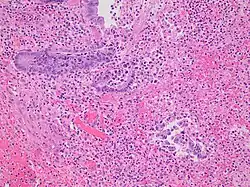

Pathology

Even for clinically certain appendicitis, routine histopathology examination of appendectomy specimens is of value for identifying unsuspected pathologies requiring further postoperative management.[75] No sign of appendicitis in specimens, negative appendectomy, varies but has been estimated to occur in 13% of specimens.[76] Notably, appendix cancer is found incidentally in about 1% of appendectomy specimens.[77][78]

Pathology diagnosis of appendicitis can be made by detecting a neutrophilic infiltrate of the muscularis propria.

Periappendicitis (inflammation of tissues around the appendix) is often found in conjunction with other abdominal pathology.[79]

-

Micrograph of appendicitis and periappendicitis. H&E stain. -

Micrograph of appendicitis showing neutrophils in the muscularis propria. H&E stain. -

Acute suppurative appendicitis with perforation (at right). H&E stain.